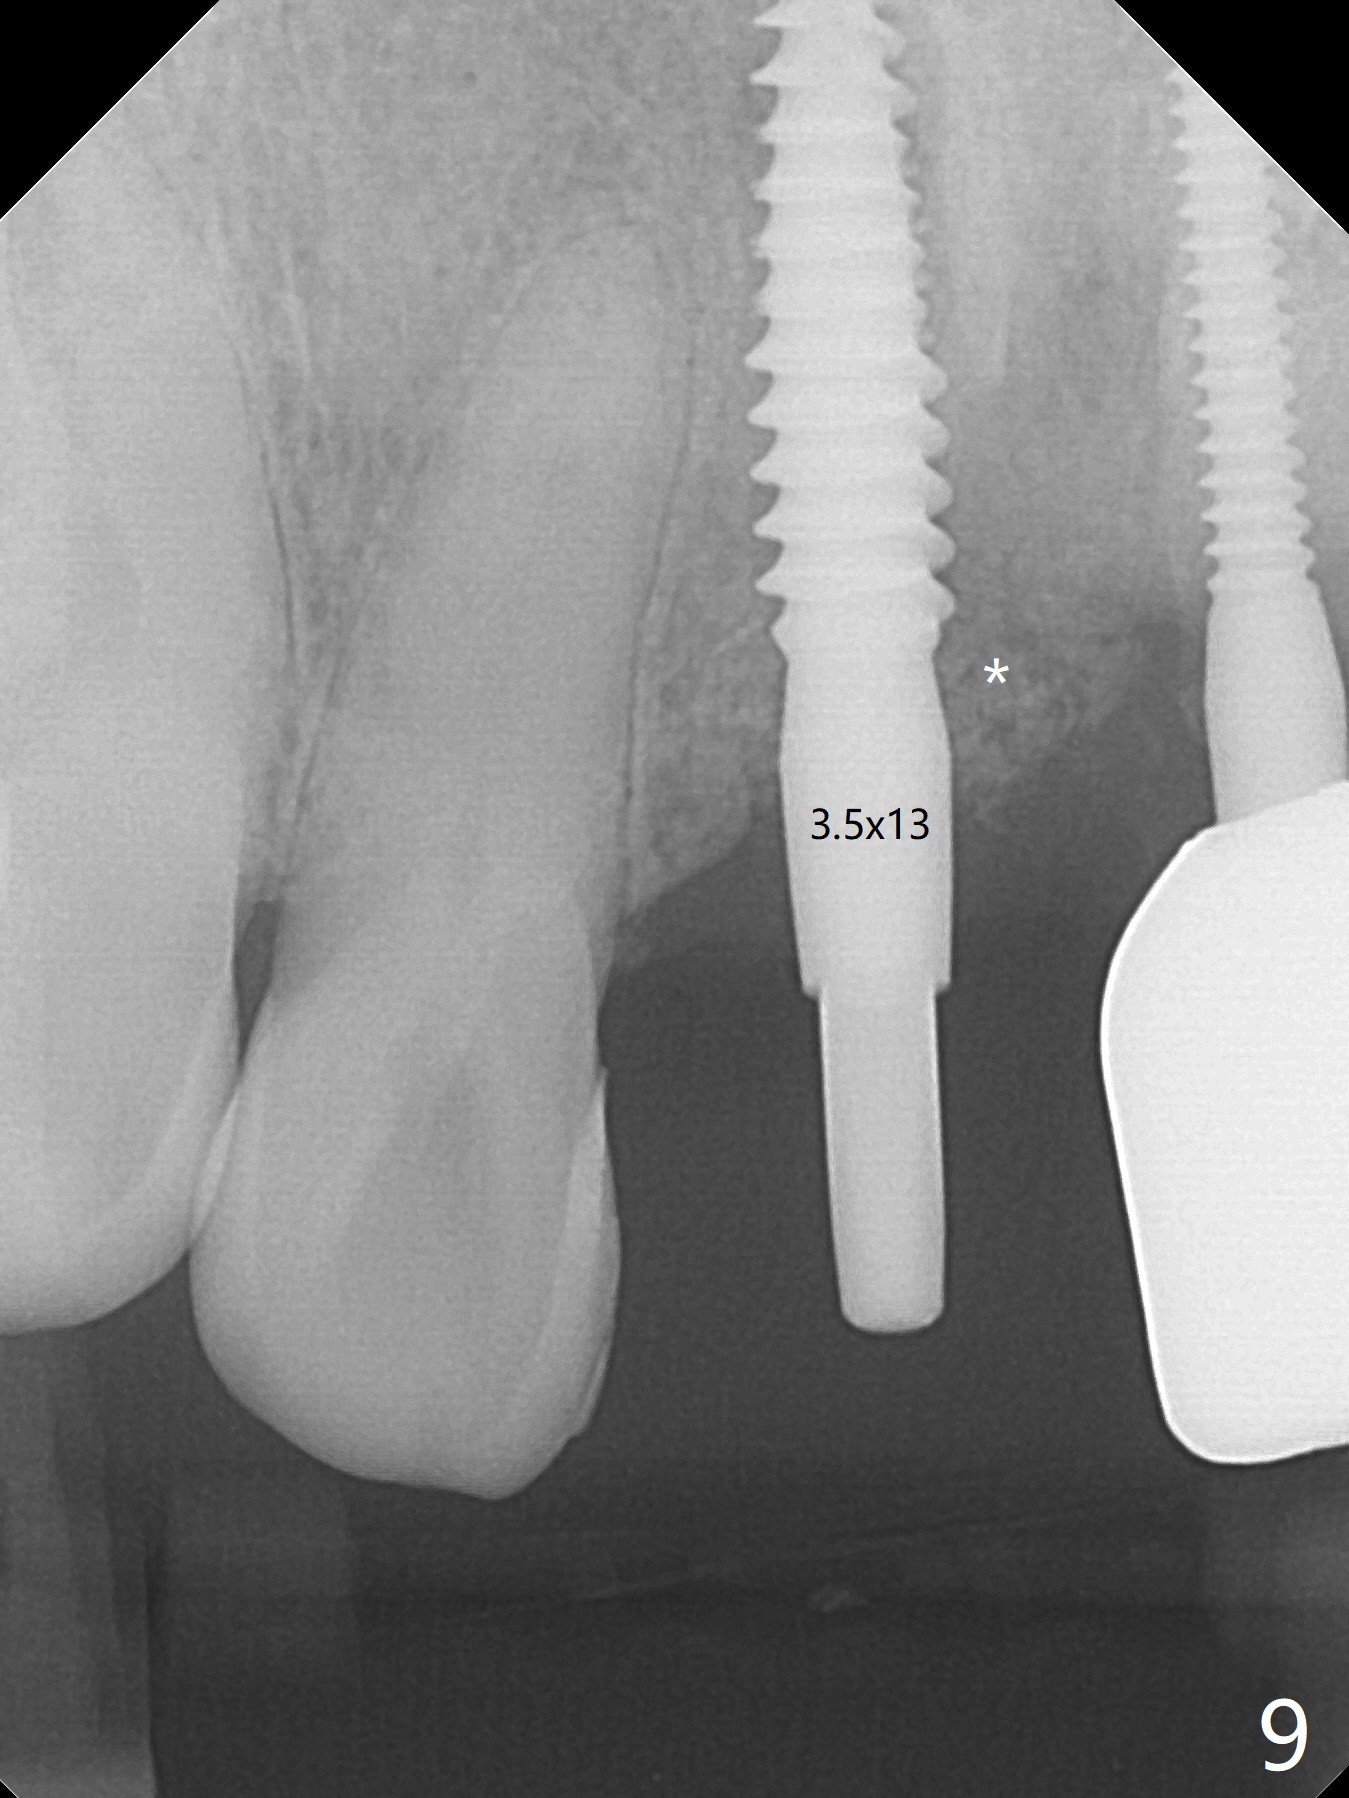

A 43-year-old man has 6 of 1-piece implants in the maxilla (#8-13). His daughter's head hits his upper anterior teeth 7 months post cementation. Exam shows that the tooth #7 has mild percussion. Nine months later the implant crown at #8 becomes displaced and loose when he bites apple (Fig.1 arrow). Forceps are used to remove the crown, leaving a concave implant site (Fig.2). After the crown is bonded to the neighboring tooth/implant crown (Fig.3 *), the patient feels pain from the neighboring tooth. The alveolus is 4.3 mm wide (Fig.4 (2.9 mm preop)), allowing 2.5 or 3.0 mm immediate implant re-placement (Fig.5). A 2.0/3.0 mm trephine bur will be used for implant removal. Try to place the new implant slightly distal to improve the trajectory (Fig.6). Particulate and/or onlay graft is an option. Prepare dummy implants. As planned, the fractured implant is removed by using a 2.0/3.0 mm trephine bur following incision (Fig.7). After use of Lindamann bur to remove the distal bone, a 3x14(4) mm dummy implant is placed with 20 Ncm (Fig.8). A longer implant could be used (3x16(2 or 4) mm), but a 3.5x13 mm 1-piece implant is placed with ~ 50 Ncm after use 3.0 mm drill (Fig.9,10). Allograft is placed around the implant (Fig.9,10 *), followed by Amnion-Chorion membrane and 5-0 PGA sutures (Fig.11). Allograft placed around the implant (Fig.9 *) appears to be able to prevent implant thread exposure 4 months postop (Fig.12). PA is taken when the crown is cemented (Fig.13). Four months postop cementation of #8 crown, the patient returns because of #9 mobility (Fig.14). In fact the implant fractures when the loose crown is removed with forceps; there is bone loss at #10. Bone graft will be placed at #10 with sticky bone (PRFx1), while the implant at #9 is redo. The ridge is wide enough for a 3.5x10 mm implant (Fig.16 (CT taken when #8 implant fractured)). Also prepare Tatum angled 1-piece implant. The 2 mm implant is too thin when occlusion contact at #10-13 is incomplete. The crowns will be redone when the implant at #9 is osteointegrated.